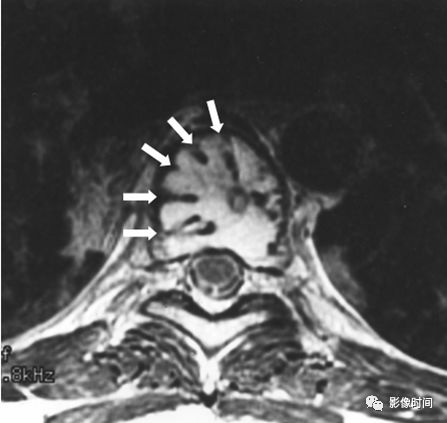

哑铃征(Dumbbell sign),又称脊柱肿瘤哑铃样表现(Dumbbell appearance of spinal tumors)

所谓哑铃征指的是肿瘤既有椎管内部分也有椎旁部分,其通过椎间孔的部分缩窄(红箭),形似哑铃型,故而得名。此征象最常见于神经鞘瘤,还可以见于神经纤维瘤、神经节细胞瘤、神经母细胞瘤或者脊膜瘤等。

典型病例

病例 1,神经鞘瘤,MRI 横轴位 T1WI 及 T2WI 像示神经鞘瘤跨椎管内外,呈现哑铃征。

病例 2,神经鞘瘤。MRI 横轴位 T2WI 脂肪抑制及 T1WI 增强扫描脂肪抑制像示神经鞘瘤跨椎管内外,呈现哑铃征。